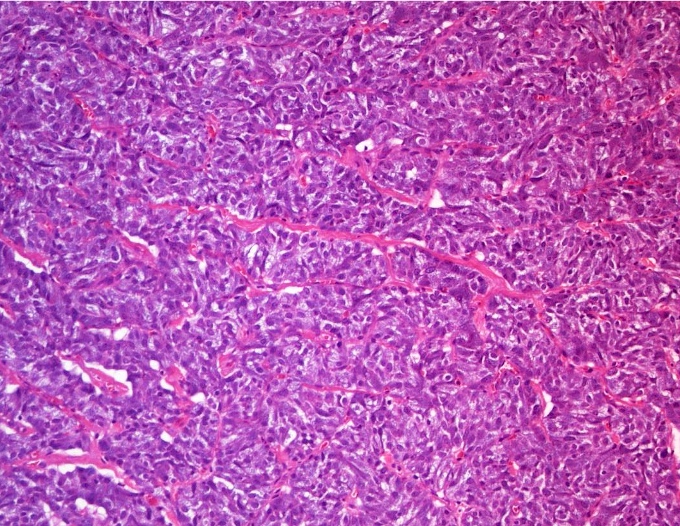

Microscopic (histologic) description

- Typical morphology: epithelioid cells with abundant, eosinophilic / amphophilic, granular cytoplasm and round / ovoid, vesicular / salt and pepper nuclei, arranged in a nested / zellballen pattern and separated by fibrovascular septae with sustentacular cells (Am J Surg Pathol 2004;28:94, World J Clin Cases 2014;2:591, Endocr Pathol 2022;33:90)

- May have focal pleomorphism, nuclear hyperchromasia, low mitotic activity or clear cytoplasm

Microscopic (histologic) images

Contributed by Theodorus H. van der Kwast, M.D., Ph.D., Michelle R. Downes, M.D., Debra L. Zynger, M.D. and David Cohen, M.B.B.Ch., M.D.